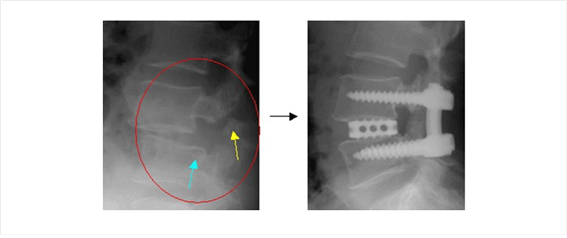

척추분리증과 척추 전방 전위증의 진단

단순 방사선 검사척추 분리증과 척추 전방 전위증의 치료